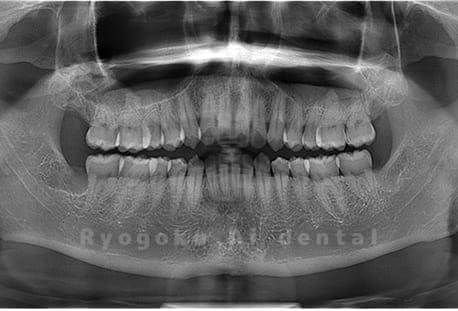

Case01

-

- 原因

- 水平埋伏智歯

- 治療内容

- 下顎の水平埋伏智歯を抜歯

<リスク・副作用>

手術後は痛み、腫れ、痺れなどの副作用が生じる場合があります。